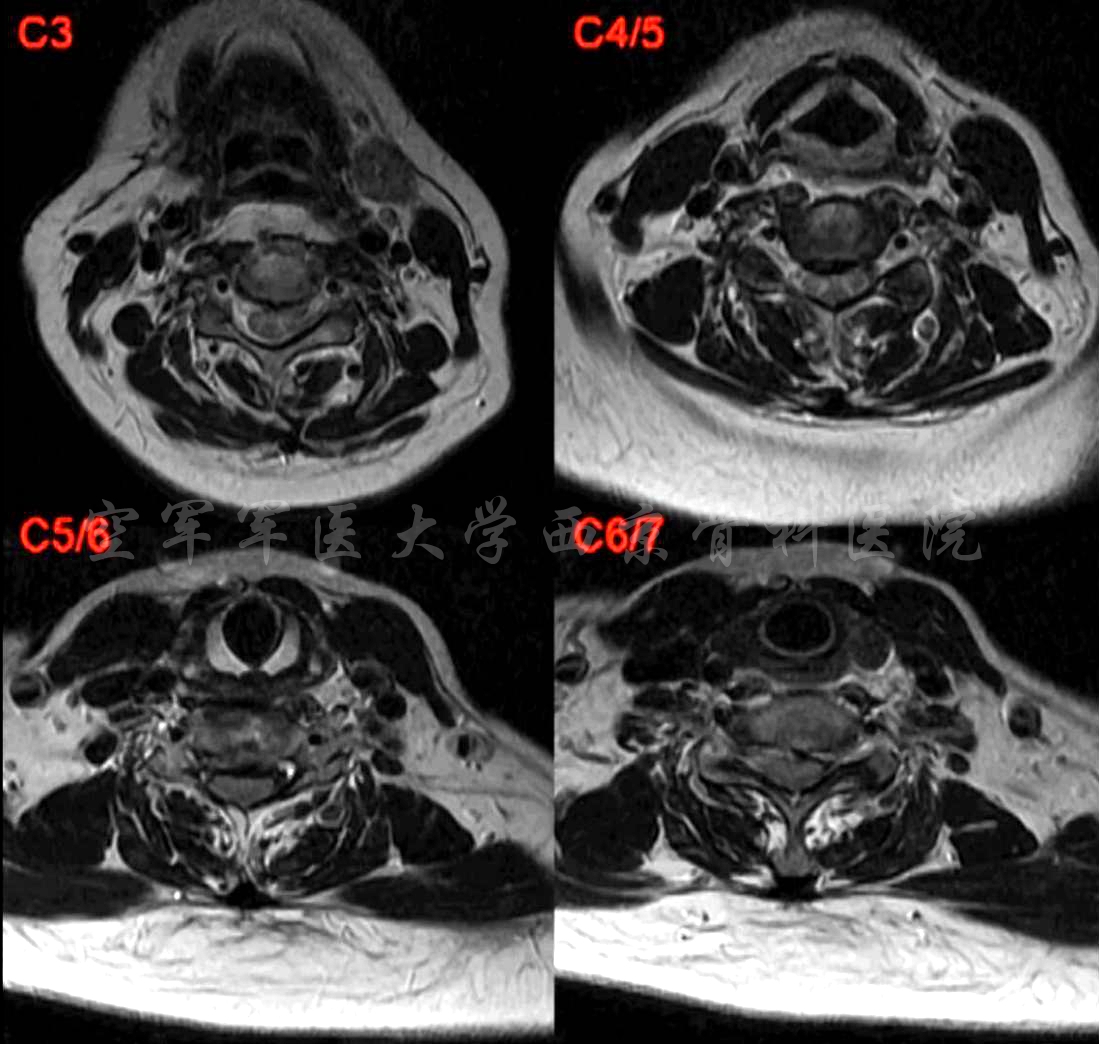

术前MRI

术前CT